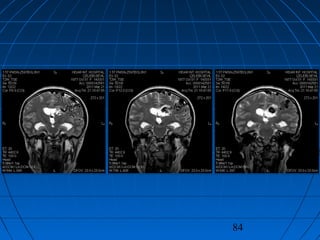

 S.Ç.: 32 yaşında kadın hastaS.Ç.: 32 yaşında kadın hasta

 Ani şiddetli başağrısı, B-KAni şiddetli başağrısı, B-K

83

CERRAHİCERRAHİ

 Sol frontoparyetal geniş kranyotomiSol frontoparyetal geniş kranyotomi

 AVM’nin total rezeksiyonuAVM’nin total rezeksiyonu